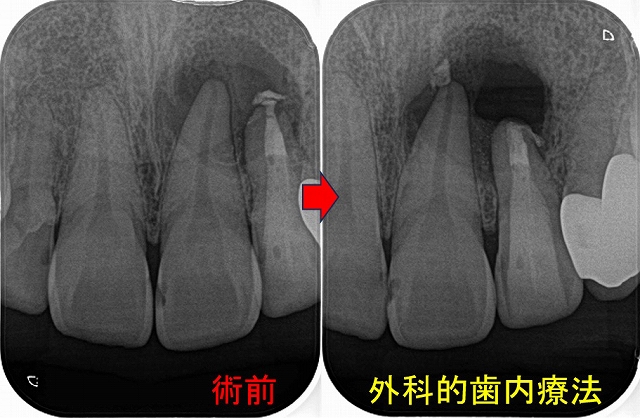

レントゲンを撮ると

はっきり根尖病変写っているんですけど・・・

過去に抜髄をしているようですが、4根管中1根(口蓋根)しか治療していない感じ

治療は2回で仕上げました。

病変の原因と思われる、MB,MB2もガッタパーチャー使用